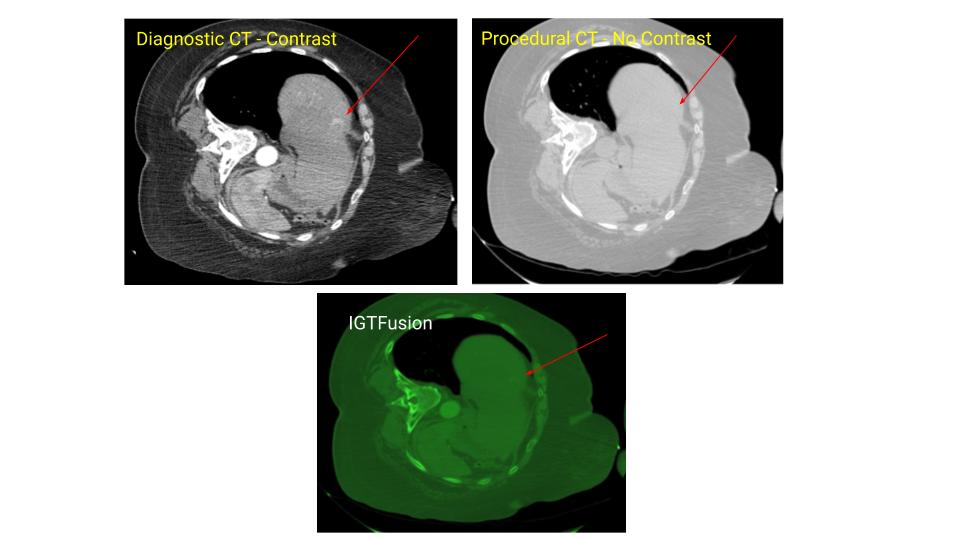

The IGTFusion System utilizes patented software algorithms to automatically align images from single and multiple image sources.

IGTFusion can visualize and register 3D image data from multiple modalities, including CT, PET, and MR images automatically.